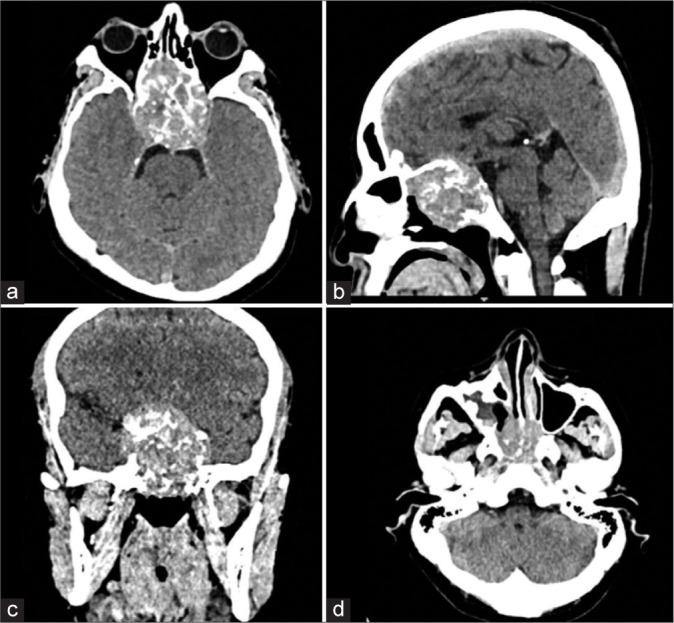

We present the case of a 39-year-old male with a 1-month history of bilateral decreased visual acuity, retroocular pulsating pain, and chromatic vision loss. A computed tomography scan of the head revealed a parasellar lesion causing chiasmatic compression, as well as clival, orbital, sphenoidal, and ethmoidal invasion. A combined transorbital and endonasal endoscopic approach was found suitable, and gross total resection was achieved. Histological analysis of the lesion established the diagnosis of a SEP. After radiotherapy, a new magnetic resonance imaging was performed, revealing a recurrence of the lesion with a high grade of invasion. The patient was treated with palliative radiotherapy, as surgical resection did not seem feasible.

我们报告一例39岁男性患者,有1个月双侧视力下降、眼球后搏动性疼痛和色觉丧失的病史。头部计算机断层扫描显示鞍旁病变导致视交叉受压,以及斜坡、眼眶、蝶窦和筛窦受侵。发现联合经眶和鼻内镜入路合适,并实现了肿瘤全切。病变的组织学分析确诊为SEP。放疗后,进行了新的磁共振成像,显示病变复发且侵袭性高。由于手术切除似乎不可行,该患者接受了姑息性放疗。